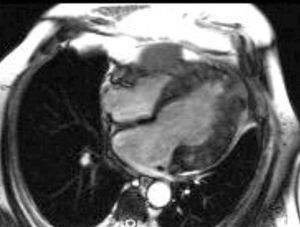

The patient was asymptomatic. Echocardiography provided limited information because of a poor acoustic window. Cardiac magnetic resonance imaging showed left ventricular dilation with severe systolic dysfunction. The right ventricular free wall presented a 30x40-mm lesion. The wall of the left ventricle was infiltrated by small lesions (Figure 1) that were hyperintense on gradient-echo sequences and T1- and T2-weighted images (Figure 2A); application of a fat-suppression pulse did not reduce the intensity of the signal (Figure 2B). Areas of late gadolinium uptake were observed in both ventricles (Figure 3). Endomyocardial biopsy did not provide diagnostic data because the lesions had not infiltrated the subendocardium. At 1 year following the diagnosis, the patient remained asymptomatic and was receiving angiotensin-converting enzyme inhibitors.

Figure 1.